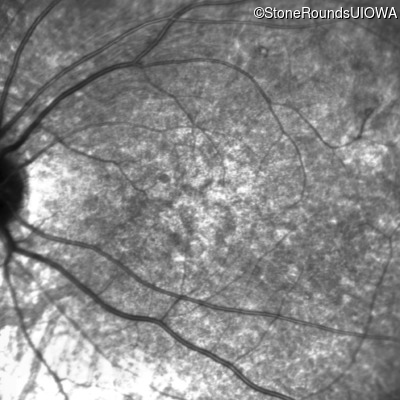

Age at visit: 8 years

This 8 year old girl had normal vision until age 6 when she failed a school vision screening. That year, she was able to play softball well, but this year she often loses sight of the ball and is often hit by it.